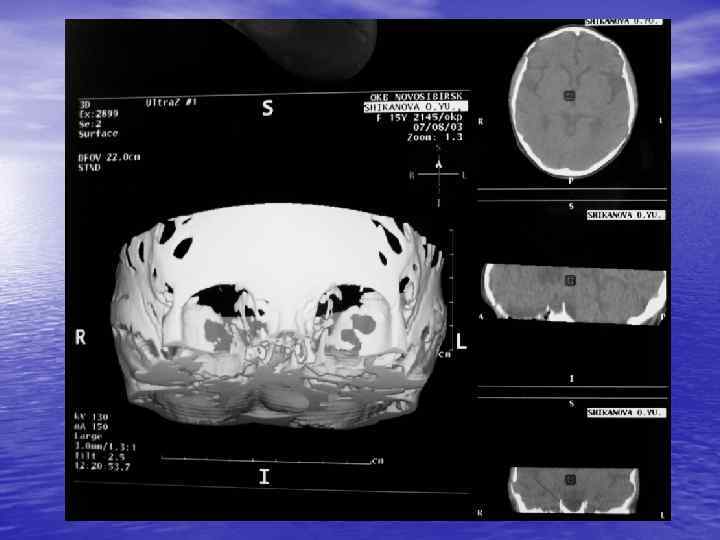

Процесс получения КТ изображения содержит три основных этапа: üизмерение, üреконструкция, üвизуализация. В настоящее время КТ можно использовать для визуализации любой части тела!

Преимущества спиральной КТ: ü Возможность проведения исследования с болюсным ü ü ü ü ü контрастированием Высокая разрешающая способность; Высокая скорость исследования; Получение высококачественных изображений костных структур; Возможность обследования всего тела; Возможность проведения исследования больных под наркозом; Возможность детальной оценки состояния крупных и периферических сосудов в условиях искусственного контрастирования; Высокая информативность метода при черепномозговых травмах в остром периоде; Ранняя диагностика ишемических и геморрагических инсультов; Метод выбора для диагностики заболеваний легких; Планирование лучевой терапии.